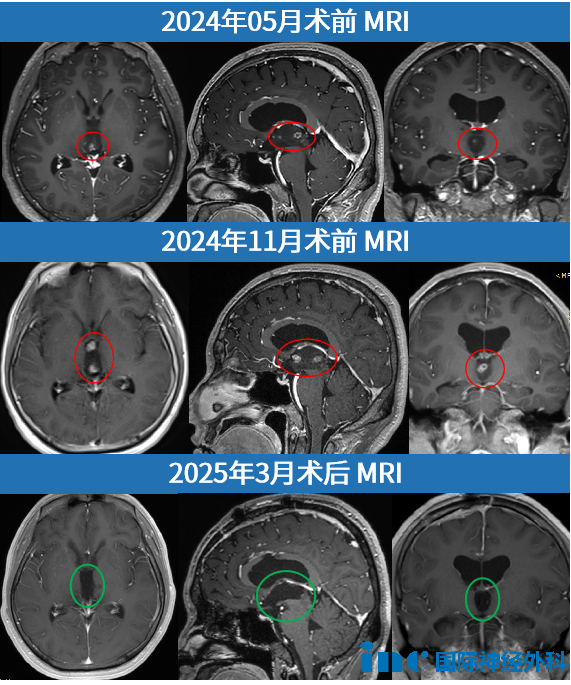

30岁的晋然(化名)怎么也没想到,一次普通体检竟揪出大脑深处的“潜伏杀手”——第三脑室肿瘤。尽管最初活检显示为生长缓慢的菊形团胶质神经元肿瘤(RGNT)WHO I级,这颗被低估的“惰性炸弹”却在暗中加速生长,最终堵塞脑脊液循环通道,再次引发严重脑积水!

肿瘤质地如顽固的“橡皮膏”,不仅填满整个三脑室,更将脑深部静脉系统层层包裹!巴教授凭借毫米级操作逐步分块切除,最终借助神经内镜360°探查死角,确保无任何残余。点击阅读:体检查出良性脑瘤为何突然狂飙,真的可以「带瘤生存」吗?